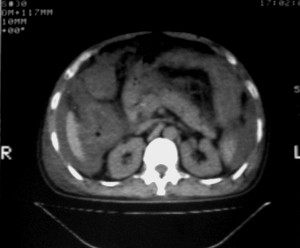

右侧肺癌术后:肝内可见多个大小不等的低密度结节影。腹腔及双侧胸腔大量积液。考虑:肺癌并胸膜及肝脏转移。

腹水,肝及右肾多发低密度影。考虑转移。

肝及右肾转移瘤,双侧胸水

右肾及肝内多发转移瘤,胸水。

1、右肺癌术后改变。2、双侧胸水、腹水。3、多发性肝囊肿,右侧肾囊肿。

目前转移或复发的依据不足,术后才一个月,个人认为还是让临床去判断,而且需结合术前常规检查,有无肝肾囊肿;另外有一个疑问:肝胃间隙内团状软组织影是胃食管交接区吗,胃腔太小了吧,有无手术史请楼主告知.